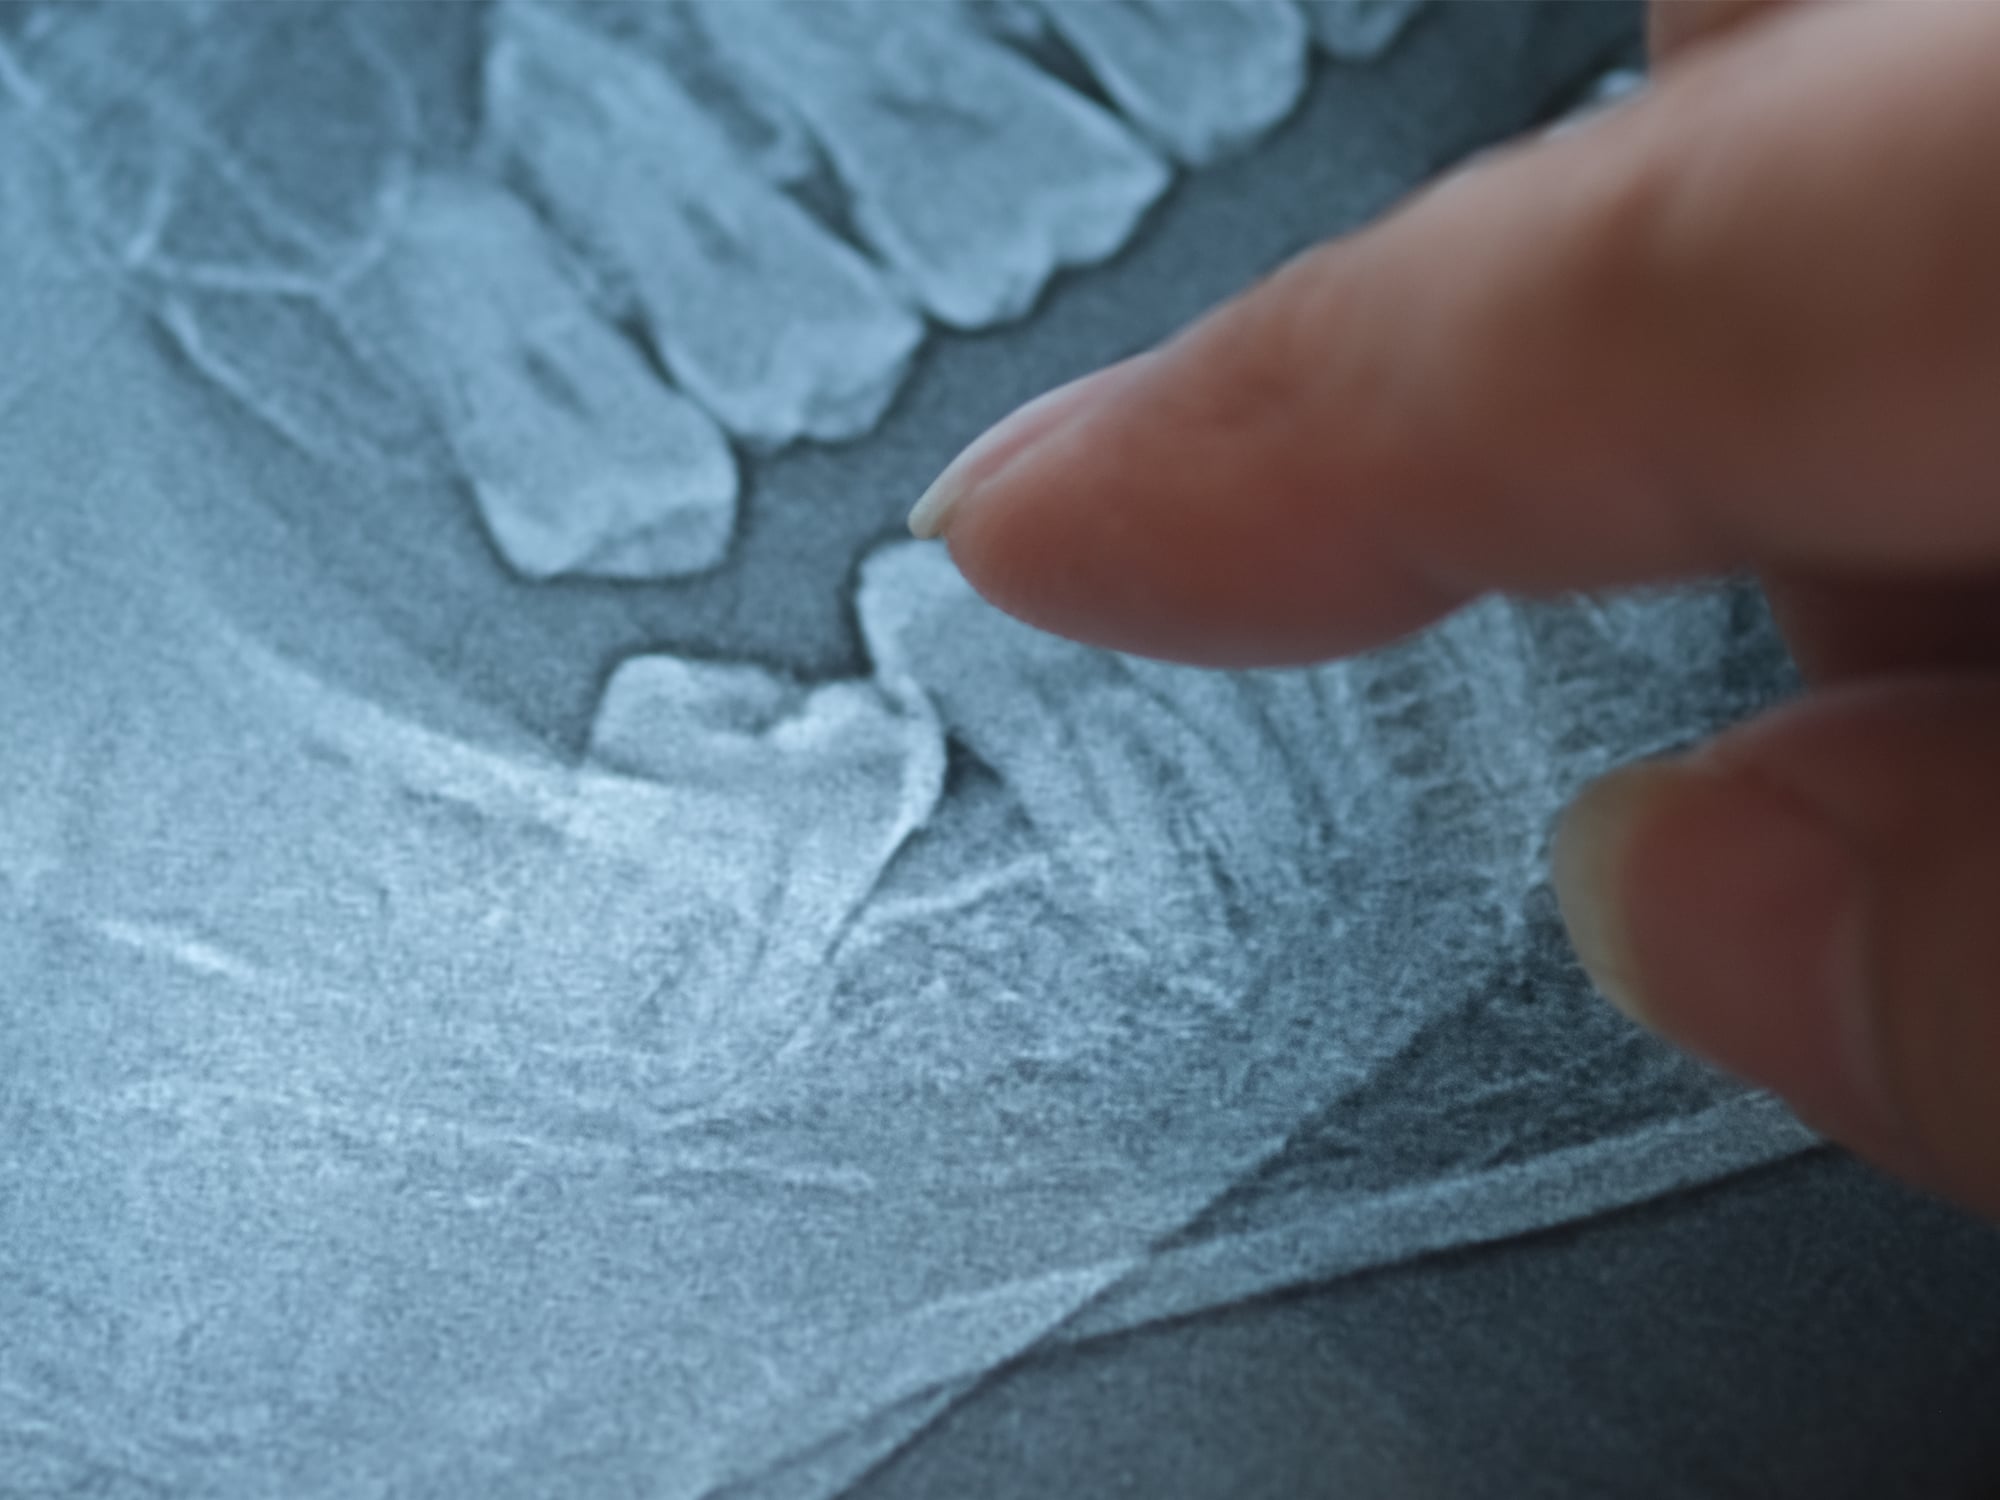

While wisdom teeth removal is considered a routine procedure, the anatomy and position of these teeth can vary significantly, especially when it comes to the roots and their proximity to nerves, sinuses, or adjacent teeth.

- 3D imaging and surgical planning for a smooth, stress-free experience

Meet with an oral surgeon at one of our comfortable centers. We’ll review 3D scans, evaluate the position of your wisdom teeth, explain the removal procedure, and answer every question you may have.